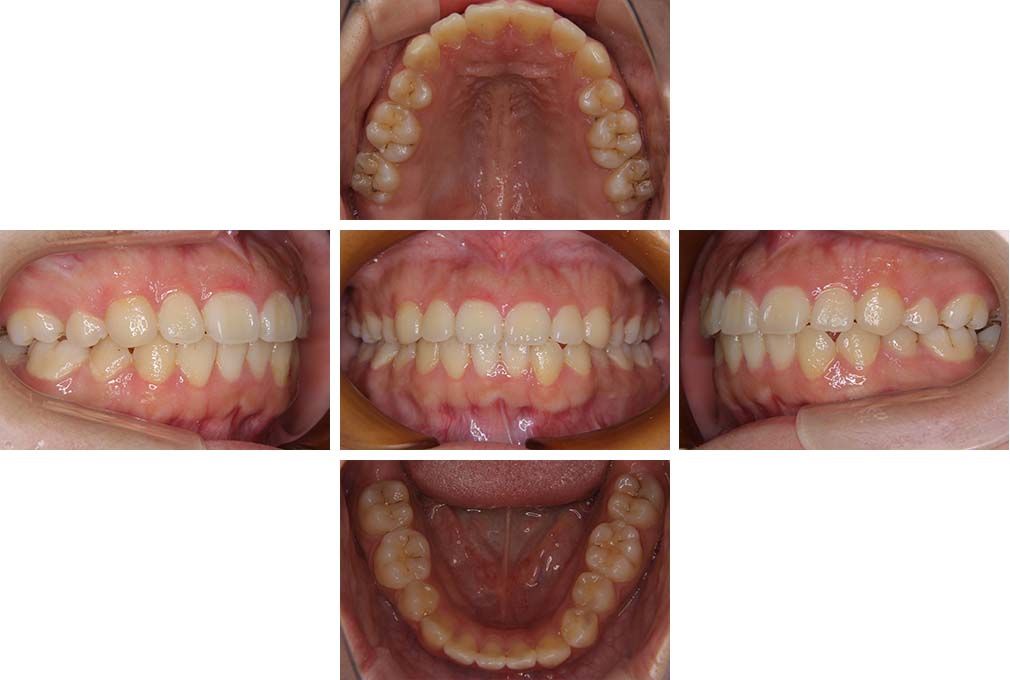

CASE:01

叢生を伴う骨格性上顎前突

初診時年齢 15歳10カ月

性別 男性

治療費の目安 約75万円程度(治療開始時)

上顎前歯の前突と叢生を主訴として来院された。大臼歯関係は左右側ともにⅡ級で上顎の方が前方に位置していた。叢生を伴う骨格性上顎前突と診断し、上下顎小臼歯抜歯を行っていただきマルチブラケット装置に顎外固定装置を併用して動的治療を行った。顎外固定装置や矯正用ゴムの使用など協力状態も良好で、動的治療期間2年0カ月、調整来院20回でマルチブラケット装置を撤去し保定へ移行した。動的治療終了後10年0カ月を経過したが保定移行時とほぼ同様の咬合状態で良好な状態を保っていた。

治療前

15歳10か月

治療後

動的治療期間2年0カ月

18歳5か月

10年経過

動的治療終了後10年0カ月

28歳5か月